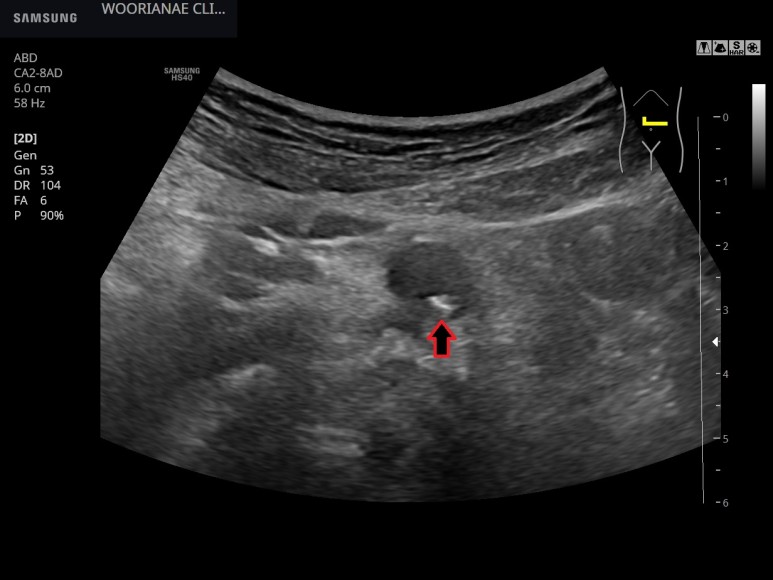

복부초음파 시행췌장 등의 고형장기는 대부분 잘 관찰되었으며 종양성 병변은 관찰되지 않았다.

사슴벌레 모양의 확장 소견(aneu rysmalchange)은 없었고 동맥 주변에 저음영 이상 소견은 관찰되지 않았다.

참조>저음영으로 보이는 후복강 섬유화